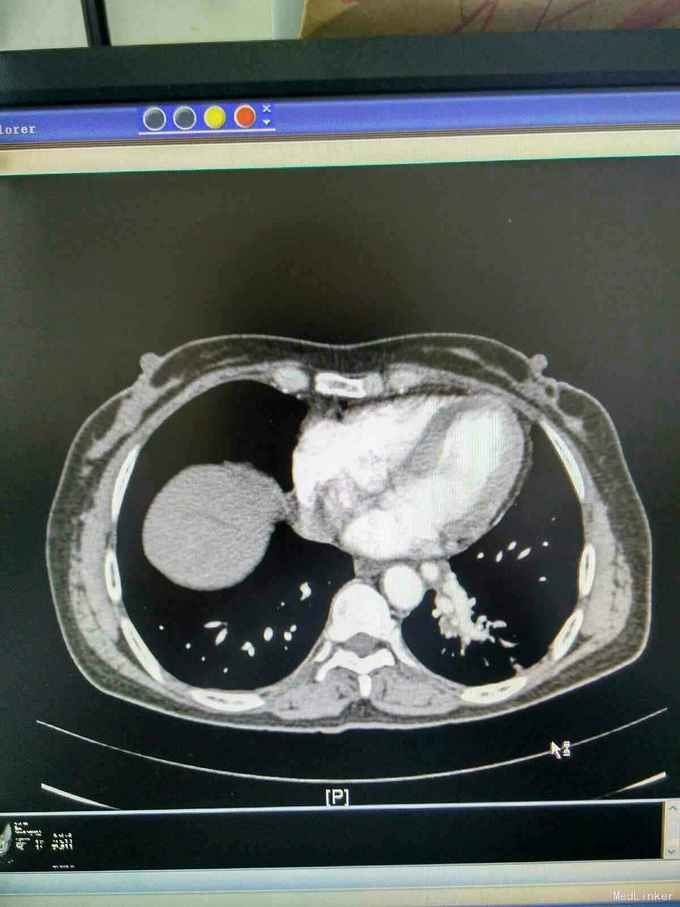

患者44岁女性,以“咳嗽咳痰间断咯血1月余”为主诉入院,入院前1月余不明显诱因出现咳嗽,呈阵发性非刺激性,咳黄白痰,每日五六口,间断咯血,色鲜红,每次10到50毫升不等,余无特殊不适,就诊当地医院摄胸部ct提示左下肺炎,予抗感染止咳化痰止血处理后症状反复,半月前复查胸部CT提示肺部阴影较前增大。

查体,神志清楚,浅表淋巴结未触及肿大,左下肺呼吸音减弱,可闻及少许湿性啰音。外院胸片示,左下肺斑片状实变阴影。

我院胸部ct增强,见左下肺病灶内见一异常供血血管,发自降主动脉,病灶周围见斑片状磨玻璃影。诊断为左肺下叶肺隔离症,转外科治疗。

患者外院胸部ct提示左下肺块影,原计划行ct引导下肺穿次活检术,我院胸部ct增强后发现,病灶为肺隔离症。遂转外科行左下肺切除术。